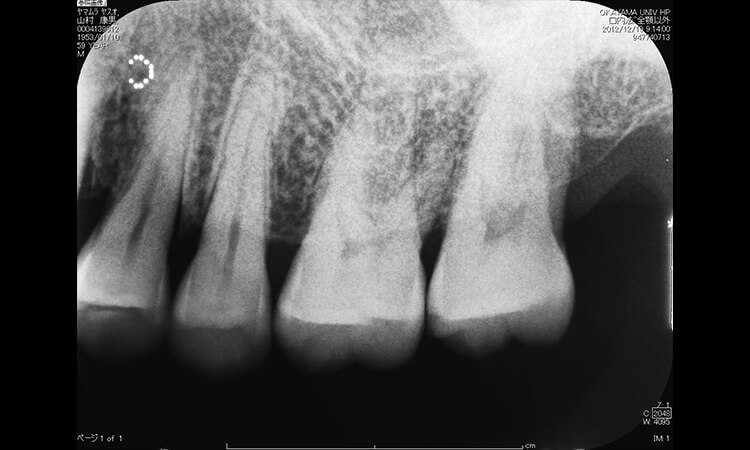

一方、デンタルX線写真より残存歯周囲に多数の垂直的骨吸収部位を認めた(図21)ため、BiteStrip®による睡眠時ブラキシズムレベルの検査を行った。その結果、2日間の検査で2日ともScore 3が示され、重度のブラキシズムを呈していることが分かった。

図21 初診時のデンタルX線写真。水平的骨吸収に加え、多数の原因不明の垂直的骨吸収を認める。